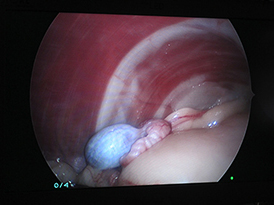

実際に腹腔鏡で確認したものもが下の写真です。

脾臓の裏の潜在精巣を超音波メスで切除し摘出しました。